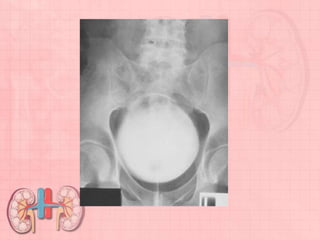

Radiographic Criteria

Structures Shown: • Entire urinary system is visualized from upper

renal shadows to distal urinary bladder. The symphysis pubis should be

included on lower margin of the IR. • After injection, only a portion of the

urinary system may be opacified on a specific radiograph in the series.

Position: • No rotation as evidenced by symmetry of iliac wings and

ribcage.

Collimation and CR: • Collimation borders to IR margins on top and

bottom to prevent cutoff of essential anatomy. • Complete arch of

symphysis pubis visible on bottom margin of radiograph, with center of

image at level of iliac crest.

Exposure Criteria and Markers: • No motion due to respiration or

movement. • Appropriate technique with short-scale contrast

demonstrating the urinary system. • Minute markers and R or L markers

visible on all series radiographs.